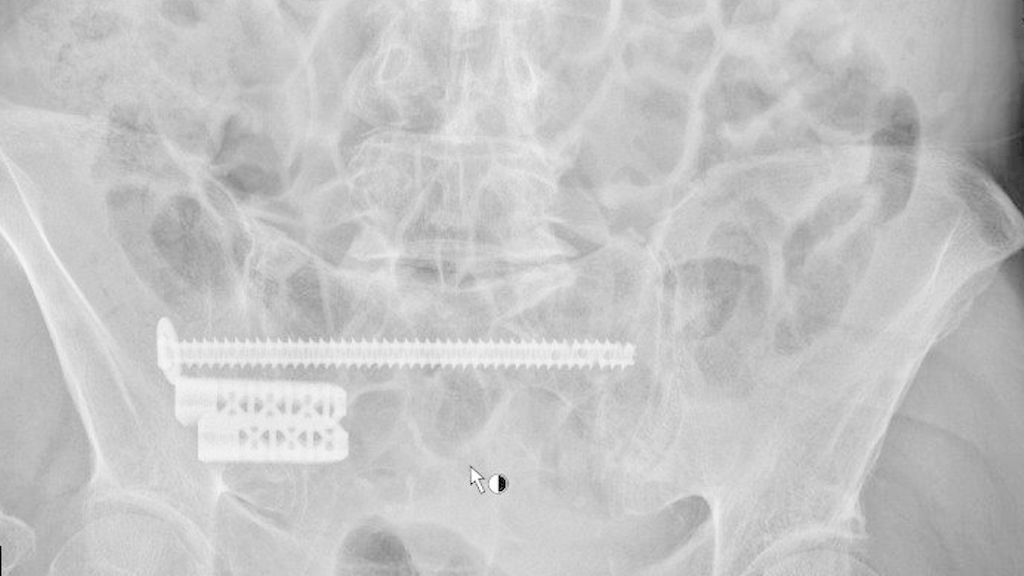

Nach Vorstellung der Patienten in unserem Traumazentrum Level I mit immobilisierenden und anhaltenden Schmerzen im unteren Rücken nach erfolgloser konservativer Behandlung wurde im Falle einer Typ-II-Fraktur eine elektive chirurgische Stabilisierung mittels iFuse in Kombination mit transiliosakralen Schrauben (TIS) (TISTM-Schrauben, Königsee Implantate GmbH, Allendorf, GER) durchgeführt (Abb. 1).

Abb. 1: Postoperatives Röntgenbild (A: Outlet, B: Inlet) einer 86-jährigen Patientin mit einer FFP Typ IIb rechts nach frustraner konservativer Therapie und daher nun chirurgischer Stabilisierung mittels iFuse® in Kombination mit transiliosakralen Schrauben (TIS); postoperativ signifikante Schmerzverbesserung mit rasch möglicher Mobilisierung

Bei Vorliegen einer FFP Typ IV wurde eine sofortige Operation mittels iFuse und TIS sowie additiver Stabilisierung des vorderen Beckenrings durch retrograde Schraubenfixierung oder winkelstabile Plattenosteosynthesen durchgeführt. Kein Patient litt an einer FFP Typ III. Alle Patienten wurden sowohl prä- als auch 3 bis 7 Tage postoperativ einer Bewegungsanalyse unterzogen. Hier erfolgte dann die Erhebung des Schmerzniveaus mittels Visueller Analogskala (VAS) in Ruhe und bei Bewegung.